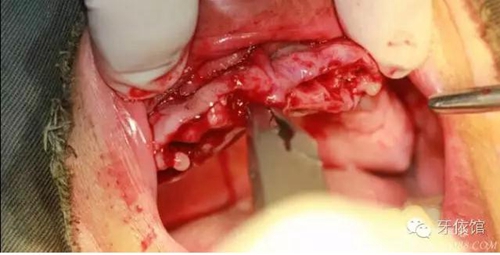

去除多余軟組織

將攜帶體重新與植體連接

將左側(cè)5(5個(gè)月前種的)連接轉(zhuǎn)移桿

縫合

取模型

安置愈合基臺